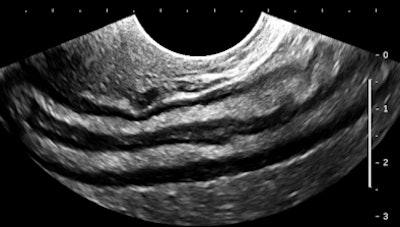

Let's have a look at some selected images from a recent study of a 30-year-old woman with uncertain dates and a positive pregnancy test:

![]() |

| All images courtesy of Dr. Jason Birnholz. |

There is a intrauterine pregnancy with a (right) corpus luteum with an intact vascular margin. A regular heart rate of 122 beats per minute implies a 6.0-week stage. The Doppler pattern has separate filling and ejection phases. The decidual boundary is thick and well implanted. But there was another unexpected finding when looking at the left ovary: